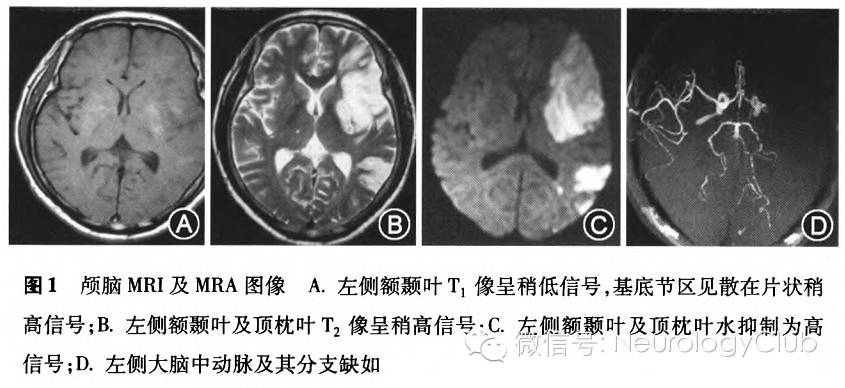

患者男,47岁,因“不能言语、右侧肢体乏力2h”于2014年10月3日入院。8h前,患者在农地里干活,不慎被大群黄蜂蛰伤,回家自行擦洗处理。2h前,患者洗澡时突发右侧肢体乏力,右手持握不稳,伴言语含糊不清,无头痛、恶心呕吐。既往高血压病史2年,服药欠规则。体查:体温37.2℃,脉搏96次/min,呼吸24次/min,血压142/87mmHg(1mmHg=0.133kPa),痛苦面容,左脸颊肿胀,面部、后背及小腿见散在多发咬伤痕迹,局部红肿,烧灼感,轻触痛,无瘀点及瘀斑。神经系统:浅昏迷,瞳孔直径3mm,对光反射灵敏,四肢肌张力稍低,腱反射(++),双侧病理征(-),余体查不配合。既往无吸烟及中毒史。实验室检查:血白细胞20.58×10^9/L,中性粒细胞0.937,嗜酸粒细胞0,单核细胞0.016;天冬氨酸转氨酶52.0U/L,肌酸激酶252.0U/L,肌红蛋白88.3μg/L,超敏C反应蛋白1.4mg/L,随机血糖10.85mmoL/L;D-二聚体0.28mg/L,纤维蛋白原2.47g/L。余肾功能、血脂、电解质、糖化血红蛋白、同型半胱氨酸、类风湿因子、乙肝、梅毒及HIV抗体等正常。急诊头颅CT:右侧基底节及左侧半卵圆中心区斑点状低密度影。排除脑出血,拟诊“脑梗死”。经地塞米松、依达拉奉、七叶皂苷、阿司匹林、醒脑静及补液等治疗,患者神志逐渐好转,第3天完全清醒,仅留有运动性失语及右侧肢体轻瘫。查颅脑MRI:左侧额颞叶及基底节区见片状境界欠清晰的异常信号影,最大横断面7.71cm×4.27cm,T1像呈稍低信号,内见散在片状稍高信号,T2像呈稍高信号,水抑制为高信号,DWI为高信号,ADC呈低信号;左顶枕叶见小片状边界欠清晰相同信号影,最大横断面2.65cm×2.62cm,周围见散在多发点片状异常信号影;MRA:左侧大脑中动脉及其分支缺如,左侧大脑后动脉主干及右侧大脑后动脉分支狭窄(图1)。心脏彩超正常。颈动脉彩超提示仅双侧颈动脉硬化,无斑块形成。1周后,患者面部肿胀基本消褪,蛰伤处结痂,但仍运动性失语,右手握力稍差,能独立行走及活动。复查血白细胞11.93×10^9/L,中性粒细胞0.72,天冬氨酸转氨酶及血糖正常。自行出院。4个月后复诊,言语表达有改善,肢体功能完全正常,但TCD显示左侧大脑中动脉血流通畅。

本例患者征象演变符合典型的脑卒中病情。就昏迷原因而言,除考虑脑梗死病灶本身影响外,蜂毒所引起的过敏性休克作用亦不能排除。虽然早期的头颅CT未见典型的责任病灶,但入院3d后颅脑MRI发现2个散发区域病灶,形态均不规则,中心区域信号强弱不等,符合既往病例报道的影像学特征。有意思的是,不仅颅脑顶枕叶分支血管未见闭塞(MRA),且4个月后TCD检查发现左侧大脑中动脉血流亦通畅,这与原有的MRA左侧大脑中动脉血管未显影恰恰相反,这为蜂毒致脑梗死的血管痉挛学说提供了有用信息。